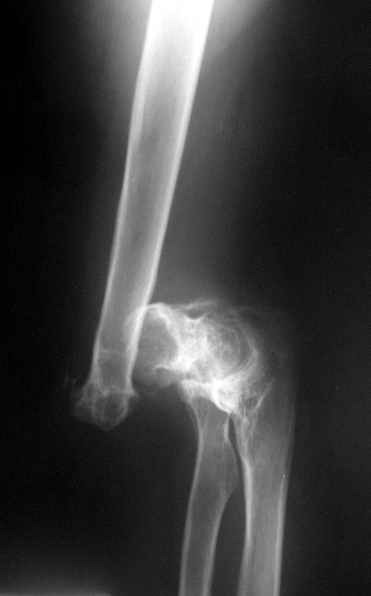

Болтающийся ложный сустав дистального плеча

Уважаемые коллеги! Обратился пациент из соседнего региона с болтающимся ложным суставом дистального отдела плечевой кости.

Срок давности травмы 6 лет. Юрист. Пользуется компьютером, пишет, т.е. движения кисти и предплечья вполне управляемы. Пациента интересует улучшение качества жизни, возможно путем эндопротезирования локтевого сустава. Я не имею опыта подобной артропластики. Далее привожу снимки после травмы, по этапам лечения, на сегодня.